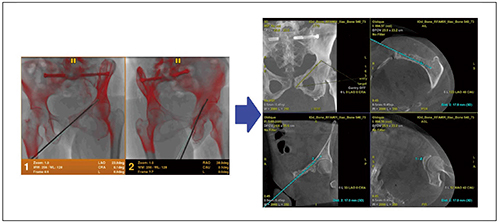

検査冒頭にCBCTを収集し,再構成されたオブリーク画像上にentry pointとtarget pointを指定すると,これらの間を結ぶ穿刺軌道が自動で算出される。さらに,entryとtargetが一直線状で重なるbull’s eye view,穿刺軌道が一番長く見えるprogress viewを瞬時に切り替えつつ,3Dロードマップとしてtargetと穿刺軌道を透視上に表示することができる(Needle ASSIST)。

Stereo3Dでは,穿刺針などの対象物が透視視野内に位置する状態で,装置が導き出した2つのアーム角度の透視画像を収集する。その後,透視画像内から対象物を自動抽出し3D再構成を行い,検査冒頭に撮影したCBCT画像上にバーチャルなラインを表示することができる(図7)。

追加CBCT撮影の代わりに2方向からの透視画像のみを用いて,3D画像上でさまざまな断面や角度から穿刺針の深度や方向の詳細確認が可能となる。手技中にほぼリアルタイムに正確性を確認しながら手技精度を高めることができ,治療効率の大幅改善,ならびにCBCT撮影回数低減による被ばく低減の双方を実現することができる。

図7 Stereo3D